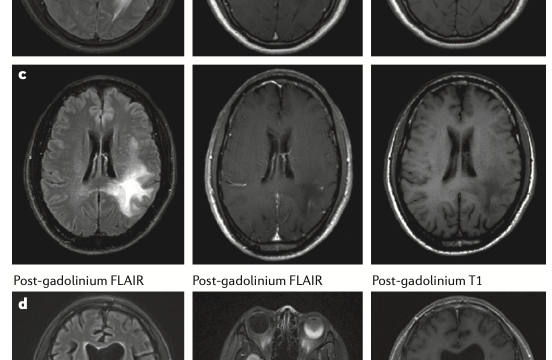

自己免疫性GFAPアストロサイトパチー